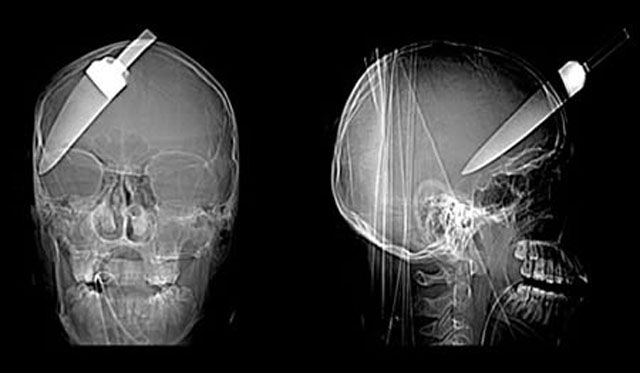

A 16-year-old cheated death when a 5-inch knife was plunged into his head. The teenager was rushed to hospital with the kitchen knife still stuck in his forehead.

The 5-centimeter nail shown in this X-ray was found after a man came to a Seoul, South Korea, hospital complaining of a severe headache. After examining and interviewing the man, doctors speculated that the nail had been the result of an accident four years before his visit, but that the man did not know the nail was lodged in his head.